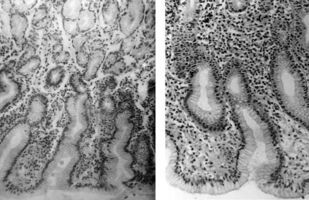

В небольшой по объему монографии представлена краткая анатомо-гистологическая характеристика нормальной слизистой оболочки желудка и двенадцатиперстной кишки, рассматривается морфологическая классификация гастритов и гастропатий, а также сущность дистрофических, воспалительных и дисрегенераторных изменений слизистой оболочки желудка при различных формах гастродуоденальной патологии. Приводятся краткие сведения об основных правилах гистологической техники, знание которых необходимо клиницисту. Основная цель пособия — дать молодому врачу представление об основах морфологической диагностики заболеваний желудка. Книга также может быть полезной для первичного образования и совершенствования гастроэнтерологов, клинических морфологов, эндоскопистов, а также для врачей других специальностей.